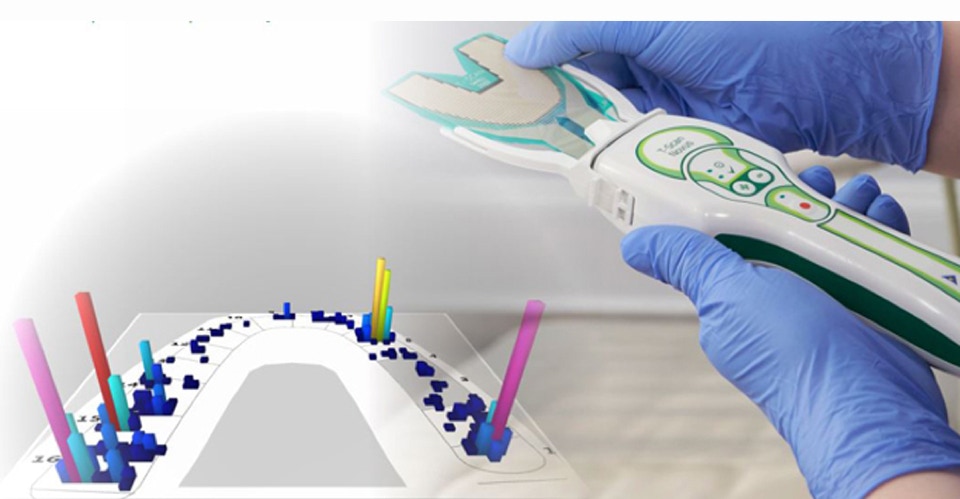

JVA Doppler Análise de Ruídos na ATM

JVA Análise de Ruídos na ATM (Zebris)

Mais de 7 milhões de casos

T-Scan

Análise de contatos

oclusais.